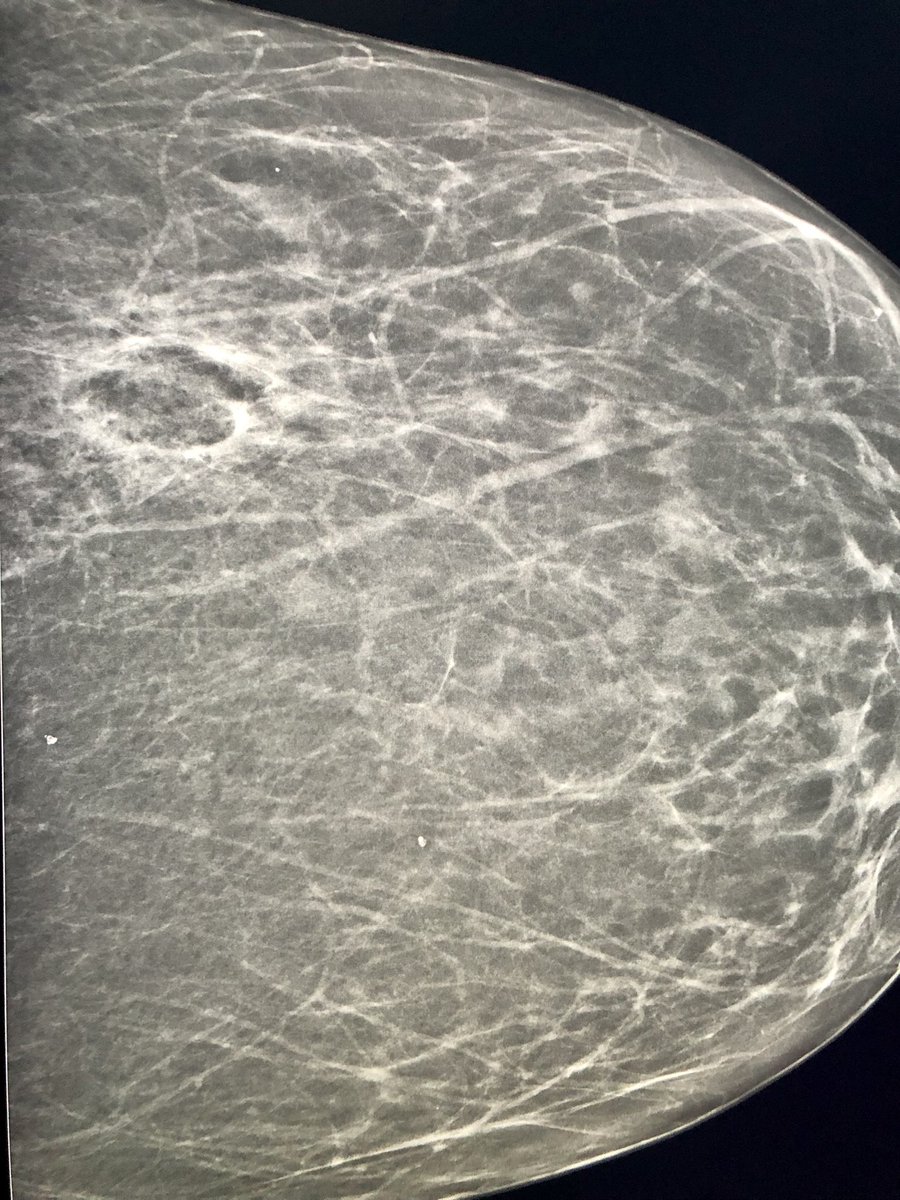

#breastcancer #Cryoablation North York General Advanced age, 6mm malignancy with HydroMark clip, tumour board recommended cryo. ICE 1.5mm 17G, protective hydrodissection, CT shows clip centrally in ice ball. Posted w permission Canadian Association for Interventional Radiology #IRad #MedEd UofT Medical Imaging thx Patrick Kennedy assisting

#breastcancer #Cryoablation <a href="/NYGH_News/">North York General</a> Advanced age, 6mm malignancy with HydroMark clip, tumour board recommended cryo. ICE 1.5mm 17G, protective hydrodissection, CT shows clip centrally in ice ball. Posted w permission <a href="/CAIRweb/">Canadian Association for Interventional Radiology</a> #IRad #MedEd <a href="/UofTMedIm/">UofT Medical Imaging</a> thx <a href="/DrPatKennedy/">Patrick Kennedy</a> assisting

Fighting #breastcancer North York General! Neoadjuvant Rx, residual IDC + clip. Developed severe neuropathy precluding Sx. Tumor board said #Cryoablation Ice Pearl 2.1, protective hydrodissection. Posted w permission ⁦@CARadiologists⁩ Canadian Association for Interventional Radiology UofT Medical Imaging thx Patrick Kennedy assist

Fighting #breastcancer  <a href="/NYGH_News/">North York General</a>! Neoadjuvant Rx, residual IDC + clip. Developed severe neuropathy precluding Sx. Tumor board said #Cryoablation Ice Pearl 2.1, protective hydrodissection. Posted w permission ⁦@CARadiologists⁩ <a href="/CAIRweb/">Canadian Association for Interventional Radiology</a> <a href="/UofTMedIm/">UofT Medical Imaging</a> thx <a href="/DrPatKennedy/">Patrick Kennedy</a> assist